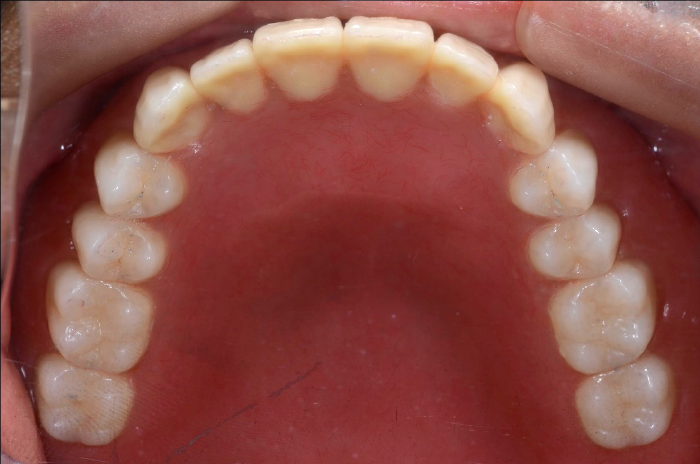

初診時の状態

歯周病により歯はグラグラの状態で、元の位置から動いてしまっていました。

また、レントゲン写真でも歯を支えている骨が吸収していることが明らかで、噛む力を十分に支えられない状態でした。

このままの状態で歯を残すことは難しく、抜歯が必要と判断しました。

初診時口腔内写真